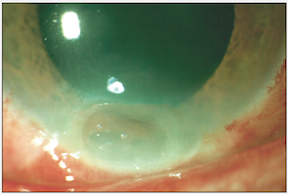

Grade II burn (above), about 1 month following injury. There is focal thinning. The cornea was treated with tissue adhesive and a bandage contact lens.

The final result of this grade II burn (above). Focal conjunctivalization.

*Images courtesy of Dr. Kathryn Colby (Massachusetts Eye and Ear Infirmary)